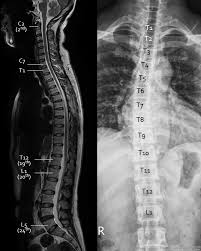

Vertebra bequem und günstig online bestellen. For each of the 12 thoracic vertebrae, there is a corresponding pair of ribs attached to them. There is a printable worksheet available for download here so you can take the quiz with pen and paper. The spinal column formed by the thoracic vertebrae protrudes posteriorly to form the convex thoracic curve of the spine. Twelve vertebrae, numbered t1 through t12 from top to bottom, make up the thoracic spine.

There are 33 vertebrae, or bones, in the spine. In addition to being connected to adjacent vertebrae, the thoracic vertebrae are also connected to ribs. The thoracic spine has 12 vertebrae stacked on top of each other, labeled from t1 down to t12. The number is the same in both males. Despite many cadaver studies focused on the cervical and lumbar spinal nerves, detailed anatomy of the thoracic nerve branches is missing from the viewpoint of painful neuropathy on the thoracic region. There are 13 thoracic vertebrae (13 pairs of ribs) in the dog and ox, but 18 in the horse. See thoracic spine stock video clips. For each of the 12 thoracic vertebrae, there is a corresponding pair of ribs attached to them. This allows the neck to move in all directions. T8 (8th thoracic vertebra) the t8 vertebra is toward the lower (caudal) end of the twelve (12) thoracic vertebrae within the central, torso section of the spine. The thoracic vertebrae form the thoracic spine, a slightly dorsoconvex bony rod, characterized by its limited flexibility. Vertebrae thoracicae) comprise the middle portion of the vertebral column and are characterized by their articulation with ribs. The thoracic vertebrae are less mobile than the cervical and lumbar vertebrae.

All vertebrae have rib elements that are usually small parts of the transverse processes. See vertebrae in the vertebral column For each of the 12 thoracic vertebrae, there is a corresponding pair of ribs attached to them. Twelve vertebrae, numbered t1 through t12 from top to bottom, make up the thoracic spine. Learn vocabulary, terms, and more with flashcards, games, and other study tools. The thoracic spine is the second segment of the vertebral column, located between the cervical and lumbar vertebral segments. Quiz over parts of the typical vertebrae this quiz has tags. The cervical spine has seven stacked bones called vertebrae, labeled c1 through c7. This allows the neck to move in all directions. It consists of twelve vertebrae, which are separated by intervertebral discs. Despite many cadaver studies focused on the cervical and lumbar spinal nerves, detailed anatomy of the thoracic nerve branches is missing from the viewpoint of painful neuropathy on the thoracic region. Other articles where thoracic vertebra is discussed: In this article, i will show you the animal vertebrae identification with labeled images.